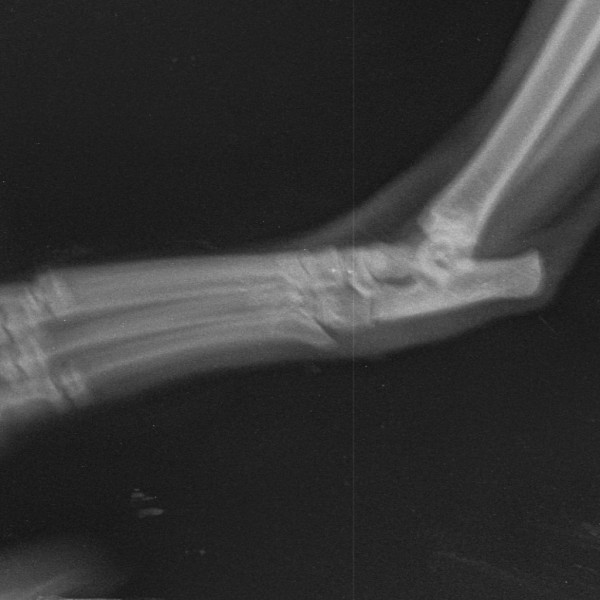

Здравствуйте. У кота, 3 года, несколько дней назад появилась кровоточащая рана в области скакательного сустава на задней конечности, кот не хромает. На улице не бывает, вероятность что поранился маленькая. Неделю назад заболел кальцивирозом, делали инъекции циклоферон внутримышечно, сейчас ничего не принимает. Повязку упорно разлизывает, то есть рана либо зудит, либо болит. Вет врач точного заключения сделать не смог, назначил антибиотики и обезболивающее, предположил что это психогенное разлизывание и имеется вывих. Подскажите пожалуйста мог ли кот вывихнуть лапу или это последствия болезни или лечения от кальцивироза?

Состояние на данный момент